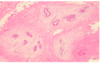

What is this showing?

Apocrine metaplasia, which is almost always benign